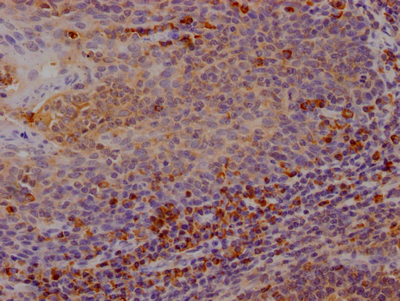

ApplicationELISA, IHC; Recommended dilution: IHC:1:50-1:200